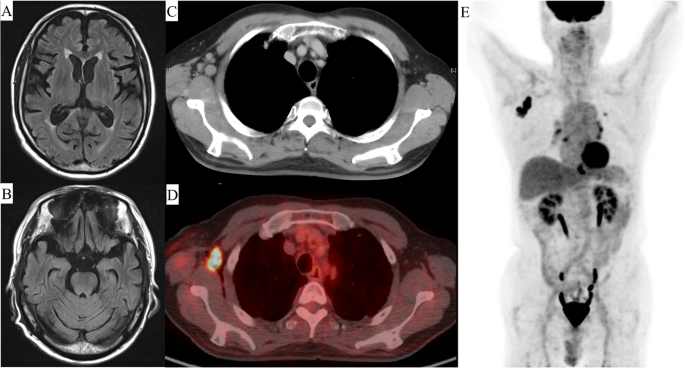

Laboratory data on admission revealed the following: hemoglobin, 13.6 g/dL; platelets, 173 × 109/L; white blood cell count, 5.1 × 109/L; lactate dehydrogenase, 164 U/L; soluble interleukin 2 receptor, 365; erythrocyte sedimentation rate, 22; and antinuclear antibody, 1:320. Examination of the cerebrospinal fluid revealed no white blood cells, slight elevation of protein (57 mg/dL), presence of oligoclonal bands, and absence of myelin basic protein. A magnetic resonance scan of the brain did not show a signal change in the parenchyma (Fig. 1a, b).

Image findings. a Magnetic resonance imaging on admission to hospital reveals no parenchymal signal change. b Computed tomography (CT) before treatment reveals an enlarged lymph node in the right axilla (1.9 × 2.2 mm). c 18F-fluorodexyglucose (FDG)-positron emission tomography (PET)/CT shows limited FDG uptake (maximum standardized uptake value, 29.13). d 18F-FDG-PET/CT shows no FDG uptake other than in the lymph node in the right axilla

Next, we performed computed tomography (CT) to identify the primary tumor, which showed an enlarged lymph node (1.9 × 2.2 mm) in the right axilla (Fig. 1c). 18F-fluorodeoxyglucose-positron emission tomography/CT showed limited fluorodeoxyglucose uptake (maximum standardized uptake, 29.13) in the same location (Fig. 1d, e) but no other mass.

At the time of diagnosis of NLPHL and PCD, the patient had a SARA (Scale for the Assessment and Rating of Ataxia [13]) score of 16. We initiated R-CHOP (rituximab 375 mg/m2, cyclophosphamide 750 mg/m2, doxorubicin 50 mg/m2, vincristine 1.4 mg/m2, and prednisolone 60 mg/m2 for 5 days) and high-dose intravenous immunoglobulin (400 mg/kg for 5 days) in the expectation of an effect of rituximab and high-dose immunoglobulin on paraneoplastic syndrome [14, 15]. The patient’s neurologic symptoms gradually improved after initiation of R-CHOP. After the second cycle of R-CHOP, CT indicated a near complete response (Fig. 1d), and no oligoclonal bands were detected in the cerebrospinal fluid, which was also considered evidence of a therapeutic effect. Therefore, we added limited field radiation (39.6 Gy/22 fr) and weekly rituximab monotherapy (375 mg/m2, 6 cycles, total of 8). His symptoms improved to a maximum SARA score of 9.